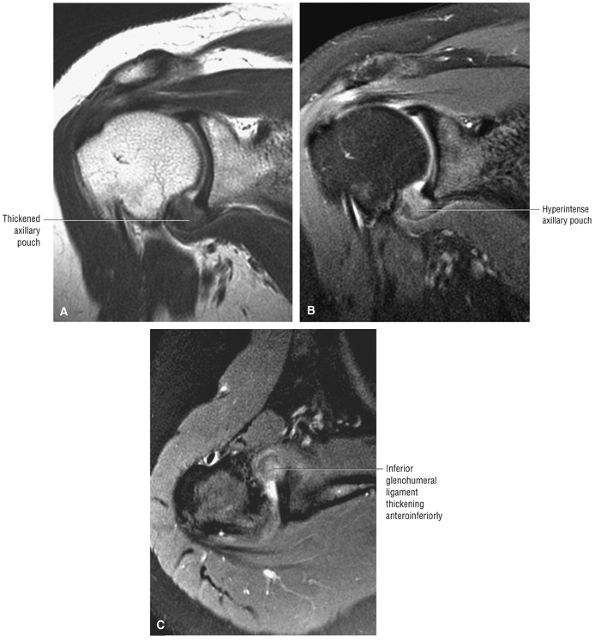

pouch that attaches to the inferior two thirds of the entire circumference of the glenoid by means of the labrum (Figs. 8.80 and 8.81).37,62 The IGHL is lax in adduction and taut in abduction and external rotation (Fig. 8.82). As it tightens with increasing abduction, the anterior and posterior bands move superiorly with respect to the humeral head. At 90° of abduction, the IGHL is the primary restraint for anterior and posterior dislocations.63 The axillary pouch is located between the anterior and posterior bands and, like the anterior and posterior bands, is lax with the arm by the patient—s side in the adducted position. The axillary pouch extends inferior to the body of the glenohumeral joint as a redundancy of thickened capsular tissue best visualized on coronal oblique images.

The inferior glenoid labrum and axillary pouch are clearly demonstrated on these oblique images. Subscapularis bursal fluid may extend inferior and medial to the inferior glenoid on anterior coronal images.

On midcoronal images, the muscle belly of the supraspinatus extends laterally beyond the glenoid before its central tendon reaches the musculotendinous junction of the rotator cuff. The axillary pouch of the IGHL, with its attachment to the anatomic neck of the humerus and the inferior pole of the glenoid, can also be seen on these images. It is not unusual to see variable

amounts of fluid in the axillary pouch in the presence of a joint effusion. Otherwise, the axillary pouch is collapsed. The presence of a glenohumeral joint effusion is associated with osteoarthritis and rotator cuff disease.42 The axillary pouch can be followed from anterior to posterior on coronal oblique images through the shoulder. -